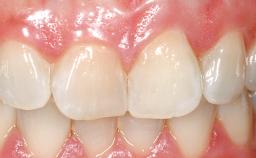

Immediate Placement of an Implant in a Maxillary Left Central Incisor Site

A 33-year-old female patient presented with an upper left central incisor that required extraction after a failed endodontic therapy. The tooth had been traumatized when the patient was a teenager and had undergone several endodontic treatments, including two apicectomy procedures. The patient was in good health and did not smoke. Clinical examination showed that the patient had a high lip line. In full smile, the gingival margins of the upper teeth were visible to the first molars. The gingival margins of central incisors 11 and 21 were only just showing. Examination of tooth 21 confirmed that the tooth was mobile and had hypererupted by 1 mm.

| Soft Tissue Contour and Volume | Slightly compromised |